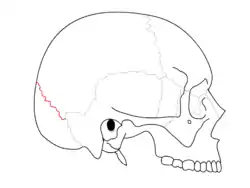

Lambdoid suture (shown in red line)

The lambdoid suture (or lambdoidal suture) is a dense, fibrous connective tissue joint on the posterior aspect of the skull that connects the parietal bones with the occipital bone. It is continuous with the occipitomastoid suture.

The lambdoid suture is between the paired parietal bones and the occipital bone of the skull. It runs from the asterion on each side.

The lambdoid suture is named due to its uppercase lambda-like shape.